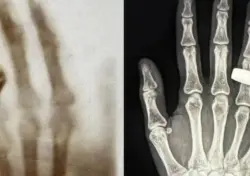

في حالة طبية نادرة، شخص أطباء الأعصاب في الصين شابًا يبلغ من العمر 19 عامًا بمرض الزهايمر، ليصبح أصغر شخص يتم تشخيصه بهذه الحالة على ...